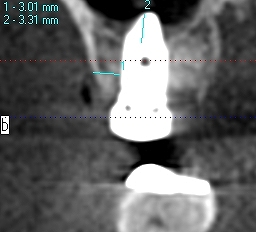

骨密度を測ります

骨の硬さを把握していきます

上顎洞までの距離はしっつかりとあるわけでもありません

この骨に上顎洞を持ち上げ5㎜幅10㎜長さのインプラントを埋入